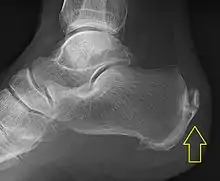

.jpg.webp)

Achilles tendinitis is usually diagnosed from a medical history, and physical examination of the tendon. Projectional radiography shows calcification deposits within the tendon at its calcaneal insertion in approximately 60 percent of cases.[17] Magnetic resonance imaging (MRI) can determine the extent of tendon degeneration, and may show differential diagnoses such as bursitis.[17]

Swelling in a region of micro-damage or partial tear can be detected via usual exam. Increased water content and disorganized collagen matrix in tendon lesions may be detected by magnetic resonance imaging.[18]